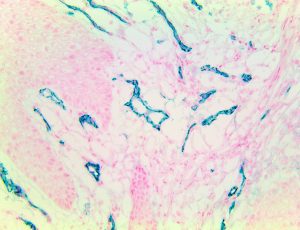

Bio SB has developed high affinity IVD monoclonal antibodies for fast immunohistochemistry (IHC) detection of melanoma, basal cell carcinoma (BCC), squamous cell carcinoma (SCC) and other Mohs surgery related conditions. Combined with our innovative IHC detection systems, we are opening the doors to a faster and more accurate immunohistochemistry applicable to Mohs surgery.

Bio SB has developed a fast, non-biotin monovalent Fab micropolymer IHC detection system for the detection of IVD antibodies for melanoma, BCC, SCC and other Mohs surgery related conditions. Our innovative IHC detection systems have opened the doors for a faster and accurate immunohistochemistry applicable to Mohs surgery.